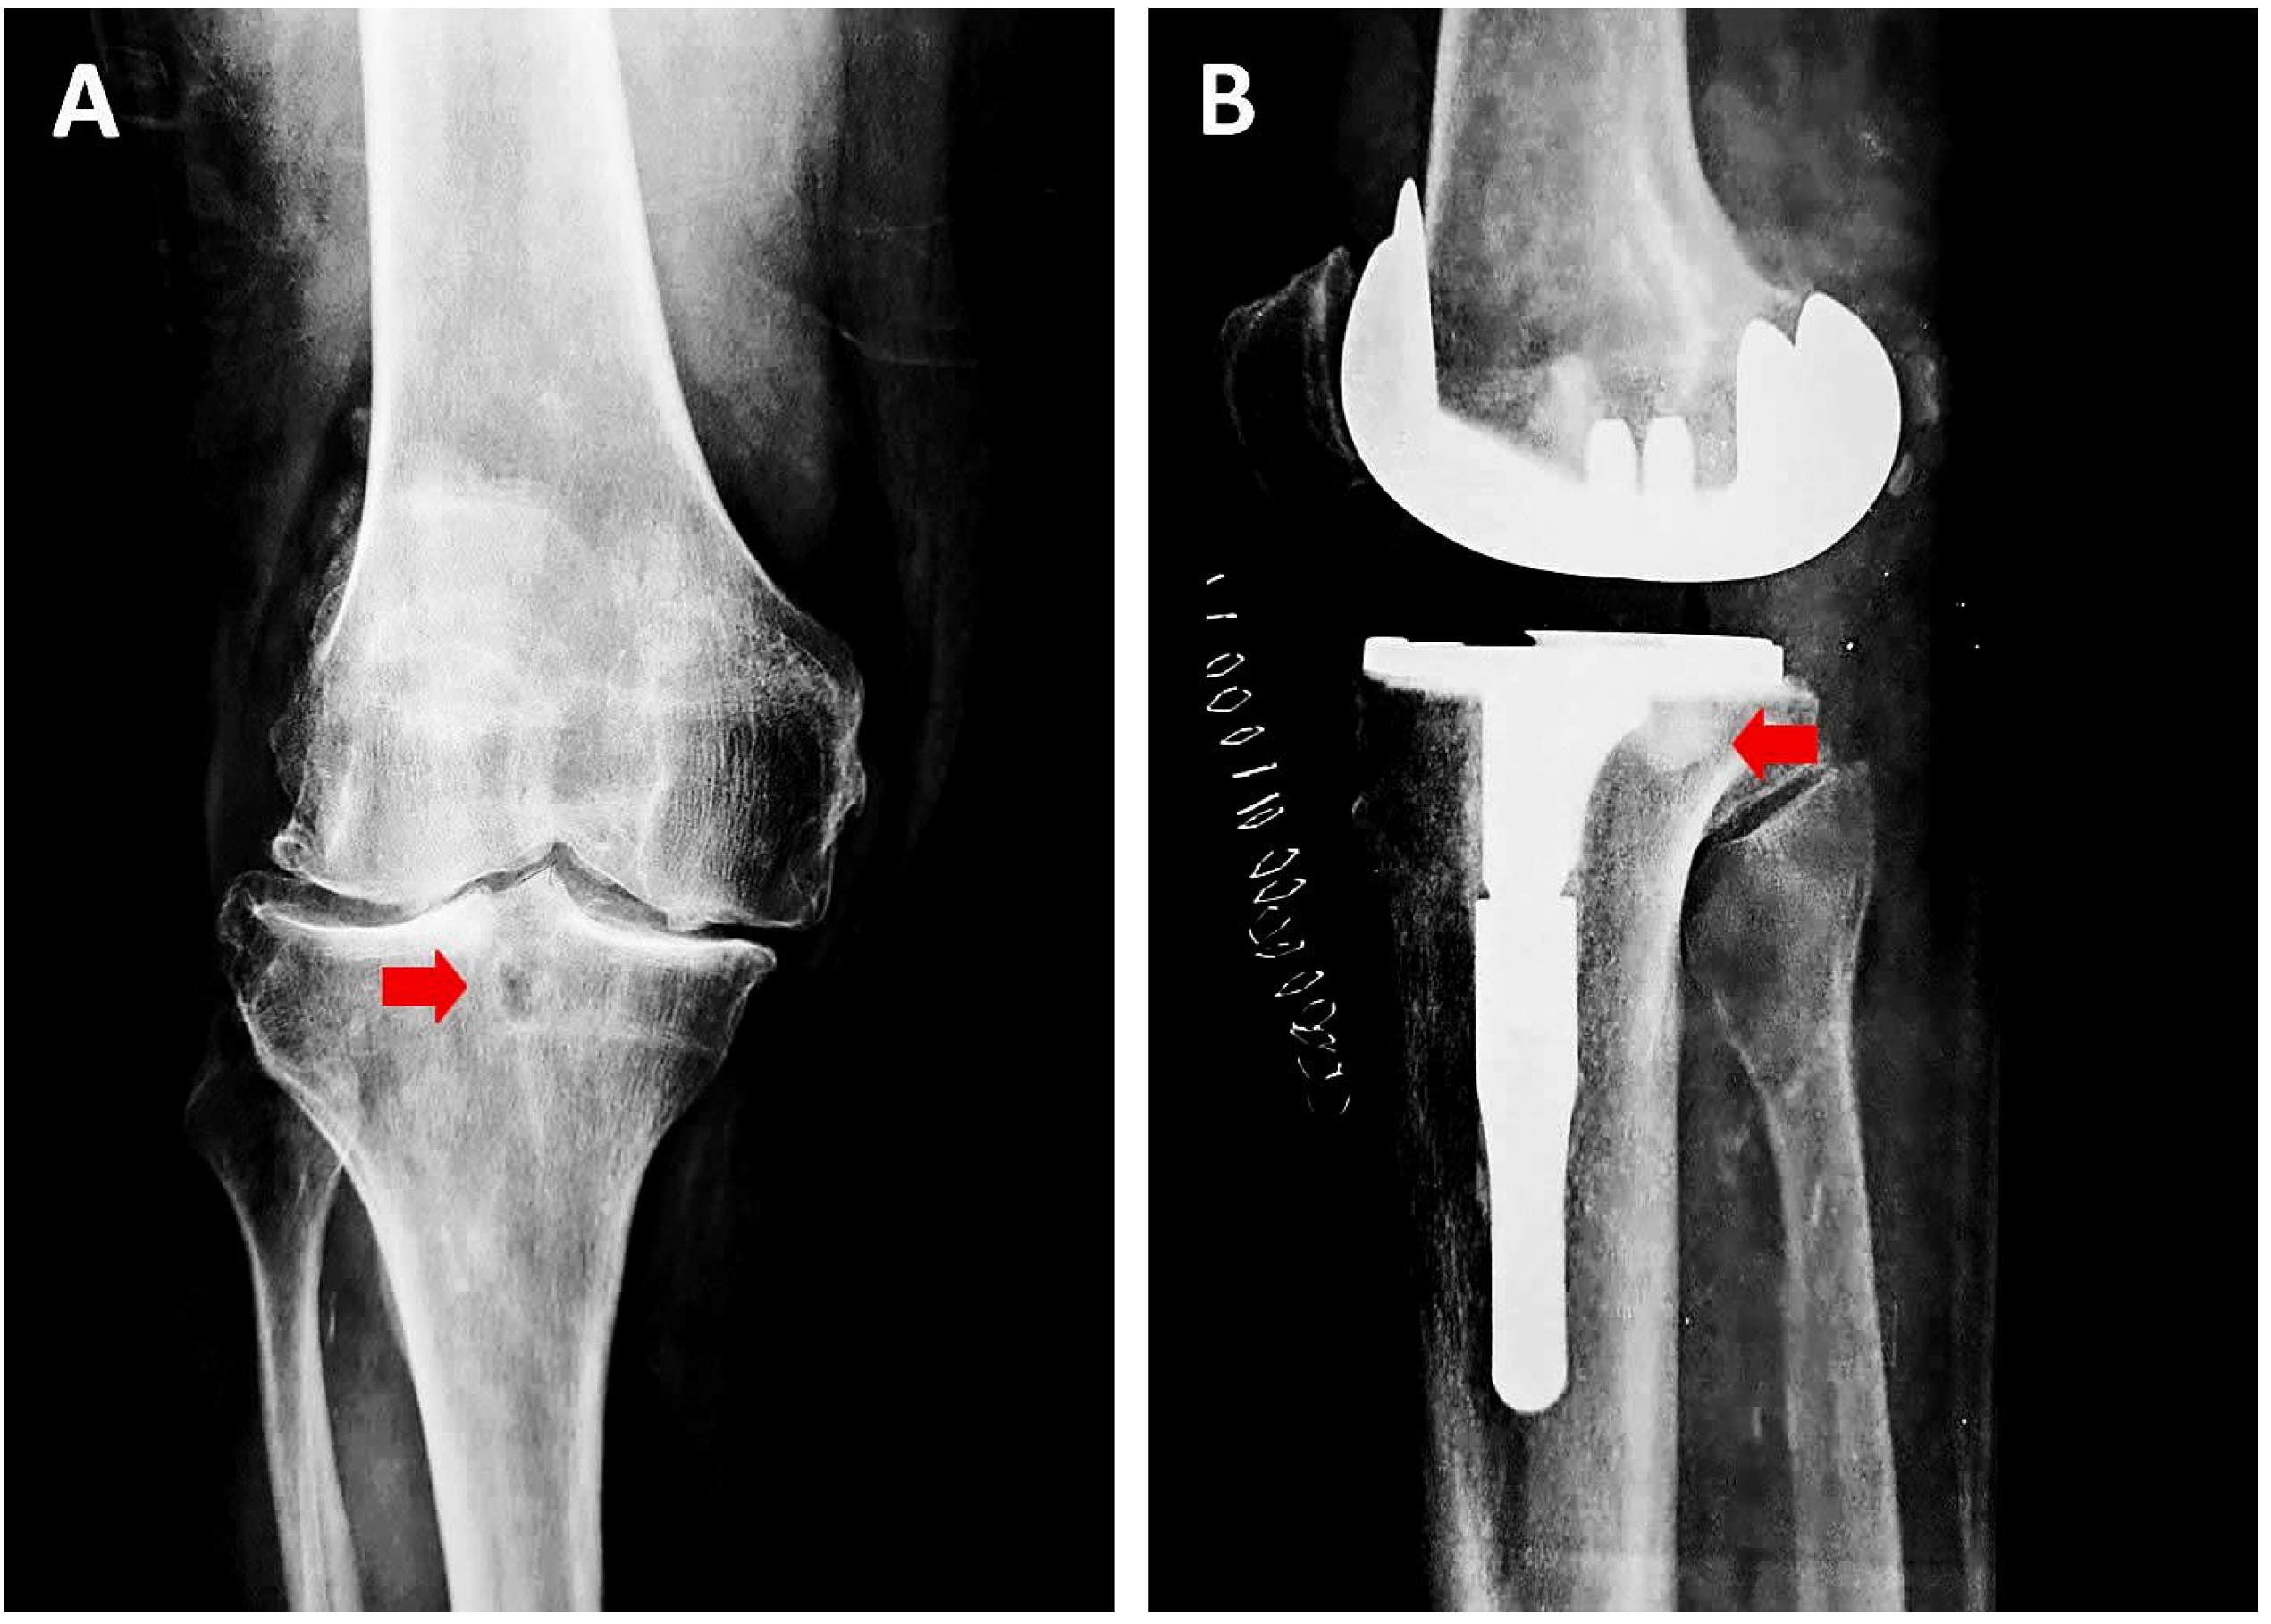

- Wang, W.; Ding, R.; Zhang, N.; Hernigou, P. Subchondral bone cysts regress after correction of malalignment in knee osteoarthritis: Comply with Wolff’s law. Int. Orthop. 2020, 45, 445–451. [Google Scholar] [CrossRef]